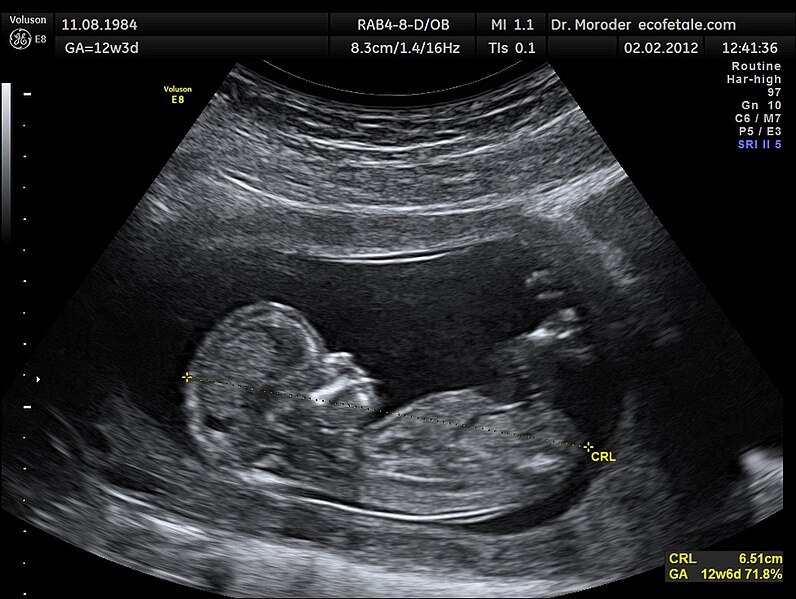

Картинка из интернета. Срок беременности по менструации здесь 12 недель 3 дня (вверху слева); по размерам плода – 12 недель 6 дней (внизу справа). Такая разница допустима, за "основной" оставляют срок по менструации. Формула для расчета срока по размерам плода привязана к сроку по менструации.